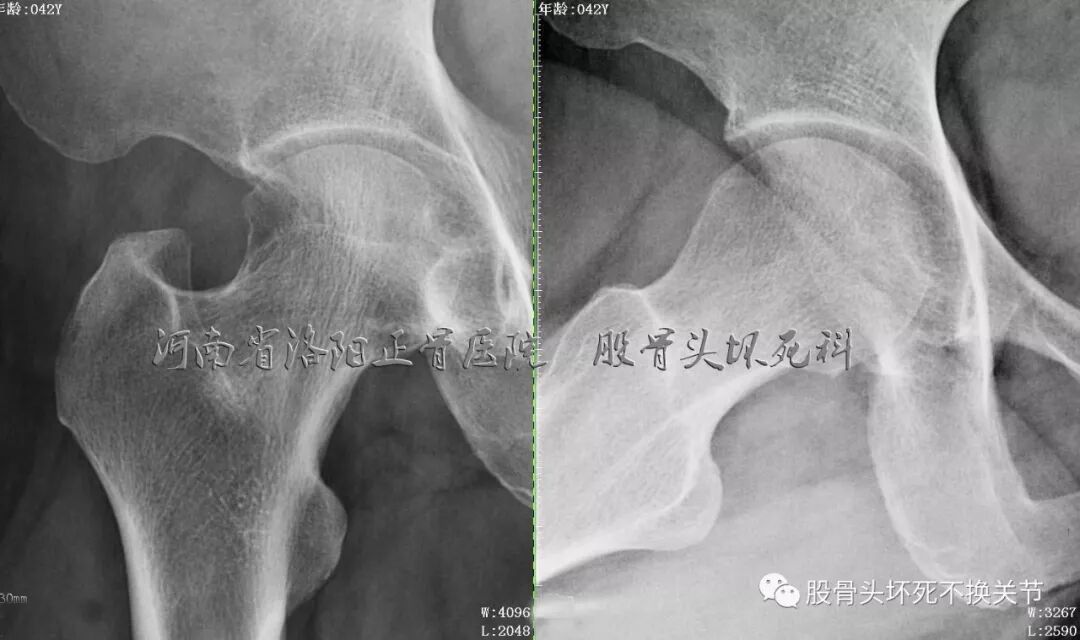

先看一下X光片:

骨盆正位片

骨盆蛙位片

右髋特写

从这些歪斜的X线片子可以看到,双髋关节并无特殊表现,双侧骶髂关节似乎轻微硬化(对于42岁生过孩子的女性来讲,不首先考虑病理原因);仔细研判放大了的右髋关节正位、蛙位片,可发现股骨头边缘轮廓并不是特别光整,与对侧相比右侧股骨近端整体骨密度低于对侧,对于一个长期患病、缺乏活动的关节来讲,不足为道,很常见。